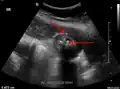

Right upper quadrant abdominal ultrasound is most commonly used to diagnose cholecystitis.[1][26][27] Ultrasound findings suggestive of acute cholecystitis include gallstones, pericholecystic fluid (fluid surrounding the gallbladder), gallbladder wall thickening (wall thickness over 3 mm),[28] dilation of the bile duct, and sonographic Murphy's sign.[13] Given its higher sensitivity, hepatic iminodiacetic acid (HIDA) scan can be used if ultrasound is not diagnostic.[13][14] CT scan may also be used if complications such as perforation or gangrene are suspected.[14]